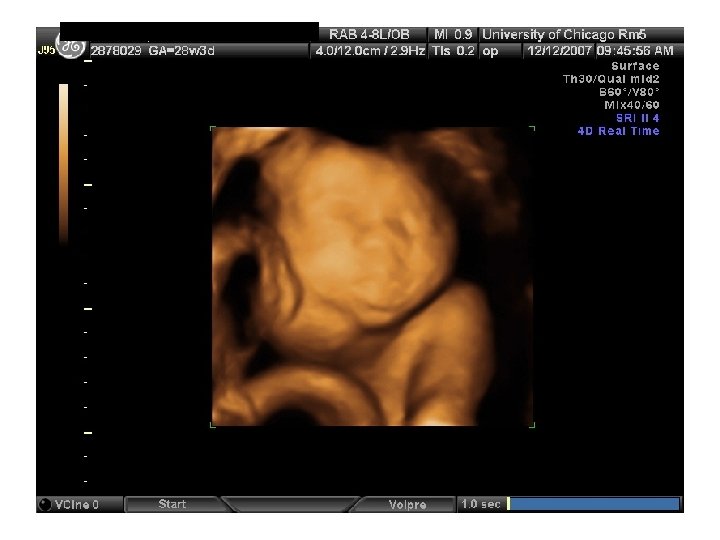

QUIZ What is Your Diagnosis? Case: Patient J. F. 30 years old, at 32 week gestation. Presented with the following pictures.

Answer: a) Trisomy 21 b) Non-immune Hydops c) Paravo virus Infection